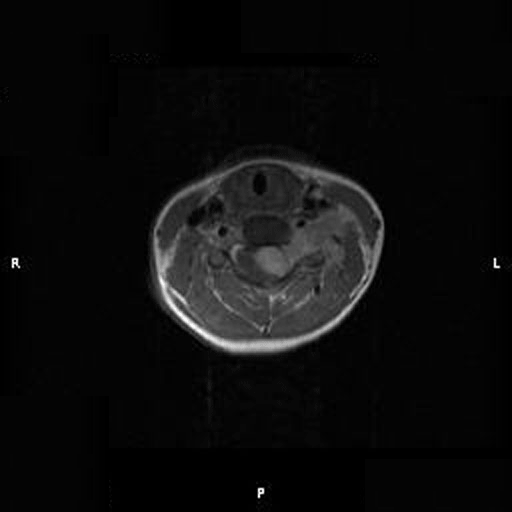

Neuroimaging of the case:

On T1-weighed images, the lesion appeared as a sausage-shaped mass that runs along the long axis of anterior portion of a spinal canal with marked compression of the spinal cord. The mass is well defined from the spinal cord and suggest an intradural, extramedullary location (Panel A). The mass abuts and slightly displaces the left vertebral artery forward. While the intracanalicular portion of the mass is well marginated, the anterolateral, extracanalicular component shows mild infiltration of the musculature. There is slightly heterogeneous enhancement of the mass. Some dural tail enhancement is also present (Panel B). On axial plane, extension of the mass through neuroforamens is well demonstrated (Panel C).